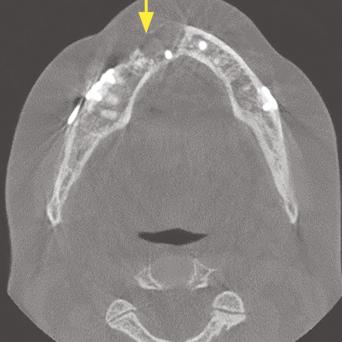

Ostéoporose : quand y penser et quelle prise en charge en MG ?

Avec le vieillissement de la population, l’ostéoporose s’impose comme un enjeu majeur de santé publique. Le dépistage et le traitement doivent devenir systématiques pour les patients ayant des facteurs de risque. Quand penser à l’ostéoporose ? Comment la rechercher ? Quand prescrire une ostéodensitométrie ? Quelle prise en charge selon le profil de la patiente ? Quel suivi réaliser ? Tour d’horizon pour le MG, algorithme décisionnel à l’appui.